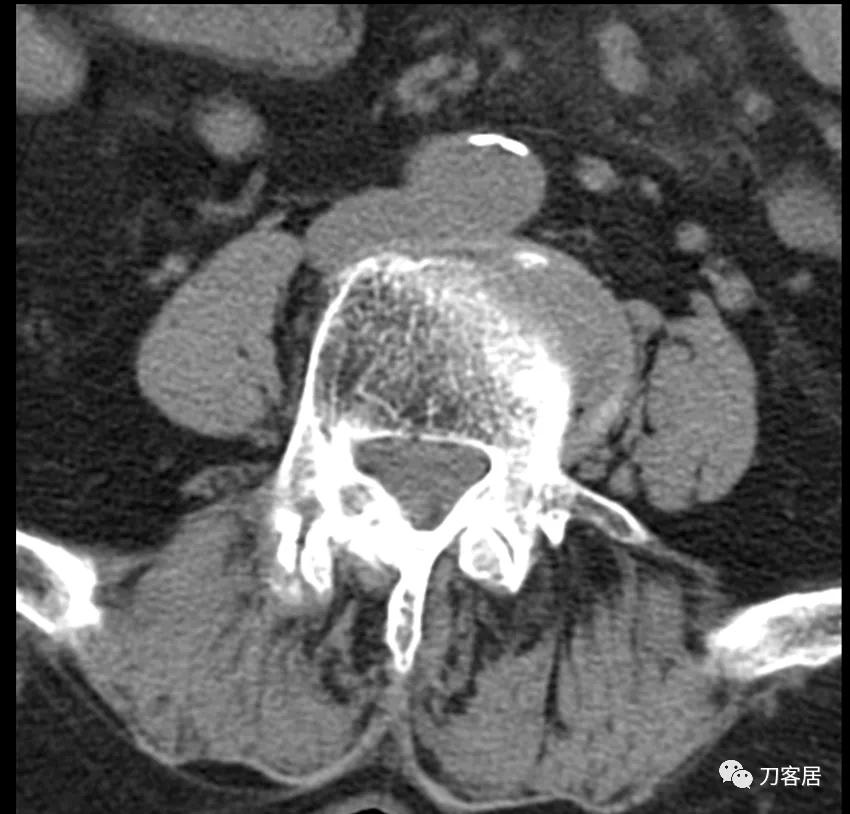

@胡满 如果是我的话,对于这种病例,首先抗骨质疏松治疗半年后再看情况,而且如果患者经济条件可以的话,建议直接使用特立帕肽,因为从患者的X线片来看,骨质疏松严重。患者的腰5滑脱应该是真性滑脱,腰5有峡部裂,腰4滑脱是退变滑脱,腰4-骶1椎管狭窄。但患者的痛苦不一定是椎管狭窄引起的。即使是做手术,患者的骨密度太低,钉子把持力不够。所以,先正规抗骨质疏松半年后再说手术吧。

患者为69岁,女性, 就诊日期:2021年11月8日。因晨起腰痛2天,就诊当日有缓解。疼痛自腰部放射至大腿后侧。2004-2005年曾有腰椎骨折病史,保守治疗后愈。

腰椎X线片提示腰5峡部裂,腰5椎体前滑脱1度,膝关节X线片提示退变增生,右侧髌股关节增生、狭窄、骨刺形成。骨密度提示骨质疏松,T值最低-3.3。2014年曾换心脏瓣膜手术,长期服用华法林,辅酶Q10, 盐酸曲美他嗪。

诊断:骨质疏松症,腰5峡部裂,腰5椎体前滑脱1度,双膝关节创伤性关节炎。